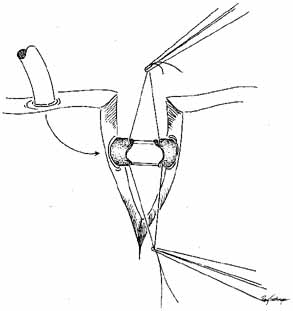

flaps.79 SILASTIC INTUBATION COMBINED WITH DACRYOCYSTORHINOSTOMY Silastic intubation is recommended as a standard portion of DCR surgery. Silastic

tubing bonded to a probe is passed through each punctum and

canaliculus to emerge from the internal common punctum (Fig. 44). The Guibor tubing system is useful. Either a groove director or

a hemostat can be used to pull the probes through the opened lacrimal

sac and out the external wound. After the two ends of the Silastic stent

is recovered from the wound, each end is passed through a 1-cm

length of Silastic tubing of slightly larger internal diameter, pulling

the thinner Silastic tubing through. The metal probes are pulled

free from the ends of the tubing. A triple tie is placed in the ends

of the Silastic tubing and pulled tightly enough to estimate the appropriate

tension of the loop of the medial canthal area. The Silastic cuff

and tubing should be placed through the bony ostium before completion

of the surgical knots, and the ends are pulled out of the nose to estimate

this tension properly. The cuff also functions in stenting the

system. A small curved hemostat passed up the nose from the external

nares is useful for grasping the ends of the Silastic tubing to pull them

inferiorly. It is useful to place the ends of the tubing in a needle

holder and pass them into the open clamps of the hemostat. As was previously

described for Silastic intubation in dacryostenosis, approximately 2 to 3 mm

of lateral movement in the tube should be permitted. This

movement can be estimated by pulling the loop with a muscle hook

at the medial canthus.  Fig. 44 A. Silastic intubation is required after excision of scars in the area of